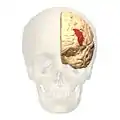

Brodmann area 46, or BA46, is part of the frontal cortex in the human brain. It is between BA10 and BA45.

BA46 is known as middle frontal area 46. In the human brain it occupies approximately the middle third of the middle frontal gyrus and the most rostral portion of the inferior frontal gyrus. Brodmann area 46 roughly corresponds with the dorsolateral prefrontal cortex (DLPFC), although the borders of area 46 are based on cytoarchitecture rather than function. The DLPFC also encompasses part of granular frontal area 9, directly adjacent on the dorsal surface of the cortex.

- Lateral view.